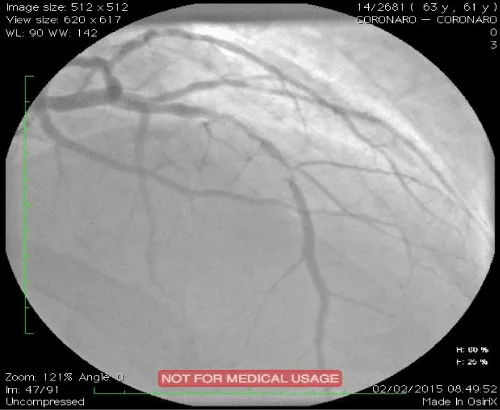

Type B lesions were the most frequent: B1=31.6% and B2=36.8%. Three patients had C-type lesions. Single-truncal affection was predominant (76.3%). Multi-truncular lesions included two-truncular ones (21.1%) and tri-truncular ones (01 patients). The SYNTAX score varied between 2 and 28 with an average value of 8.9. A balloon pre-dilation was carried out in 36.8% of the cases. Direct stenting concerned 63.2% of procedures. Twenty-one bare stents (55.3%) and 17 active stents (44.7%) were implanted. The average number of stents per patient was 1.18. The average diameter of the stents was 3.25 and the average length was 17.4 mm. The results were excellent in 94.7% of cases with a TIMI grade 3 flow and without dissection. The average hospital stay in post-angioplasty was 2.31 days [01-08 days]. Intra-hospital progression was favorable in 35 of our patients (92.1%). Two early deaths during the first 48 hours were recorded. One case of acute stent thrombosis was noted 24 hours after angioplasty. At 2 and 6 months, two cases of angina due to exercise and three cases of dyspnea stage II-III of the NYHA were noted clinically. Electrical abnormalities were mainly related to changes in the ST segment with epicardial ischemia. Nevertheless, a third death occurred following a probable angina attack less than 2 months post ATL. Echocardiography of dobutamine stress during follow-up was positive in 04 patients (12.5%). Control coronary angiography performed in two patients revealed very tight in-stent restenosis (Figure 1). The predictive factors for restenosis were dominated by a deterioration of the segmental kinetics (p=0.009), the diastolic function (p=0.002), the systolic function (p=0.003), a high post angioplasty troponin (p=0.004), the presence of calcifications (p=0.004) and a high SYNTAX score ≥ (p=0.021) (Table 1).

Figure 1: Drug-eluting in-stent restenosis of left anterior descending coronary artery in a patient with a positive stress echocardiography.

Intra-hospital evolution was favorable in the majority of cases (92.1%). However, one acute stent thrombosis and two early deaths during the first 48 hours following angioplasty, probably due to a ST were noted. Predictive factors for intra-hospital mortality were similar to those in the literature, ie, advanced age and the presence of complex and proximal coronary lesions [8-10]. These factors corresponded to our deaths cases. At short-term control, a third death occurred. The hypothesis of late stent thrombosis or short-term ISR is more likely. The FAST-MI 2005 [11] and RESCUE 2008-2009 [12] registers have a 30-day mortality rate comparable to our series, of 7% and 6%, respectively (the rate found in our study being 7.8%). In the medium term (6 months post-angioplasty), it is recommended to seek the reappearance of myocardial ischemia, silent or not, suspecting an in-stent restenosis [13]. This research can be done by a “stress test” to physical or chemical stimulation. In our study, mid-term evaluation included dobutamine stress echocardiography as indicated by recent recommendations in pauci-symptomatic patients as asymptomatic in the medium-term post ATL (Class I level of evidence A) [13,14]. This test was performed in our series between the 5th and 11th month post ATL in 84.2% of our entire sample. At the end of the examination, 04 cases were positive. Two patients had control coronary angiography that showed a very tight ISR (>90%) and a TIMI grade 1 flow. The ISR predictive factors found in our patients are comparable to the data found in the BENESTENT [15,16] and Cutlip et al. [17] studies. These predictors of restenosis were dominated by a deterioration of segmental kinetics, diastolic function, systolic function, high post angioplasty troponin, presence of calcifications and a high SYNTAX score.